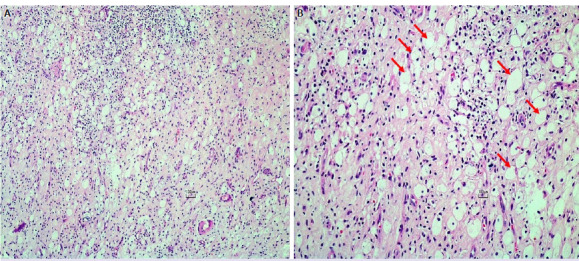

Xanthogranulomatous inflammation is a rare chronic inflammatory reaction. Appendiceal involvement in the pediatric age group is extremely rare. We present a case of xanthogranulomatous appendicitis (XGA) that was detected incidentally during the excision of a residual intraabdominal mass in an 8-year-old male patient who was treated for Burkitt lymphoma. An 8-year-old male patient who had been diagnosed with Burkitt lymphoma underwent abdominal computerized tomography for evaluation after chemotherapy. An approximately 2.5 cm mass in the right lower quadrant of the abdomen was detected, and laparoscopic excision of the mass was planned. During the operation, it was noticed that the appendix (adjacent to the mass) was golden yellow in color and abnormal in appearance, so a synchronous appendectomy was performed. The pathology result of the mass was compatible with Burkitt lymphoma. Microscopic examination of the appendix revealed that the columnar surface epithelium had eroded and been replaced by fibrin and cell debris. Inflammatory cell infiltration rich in foamy histiocytes as well as lymphocytes and sparse neutrophils that form destructive aggregates was observed in all appendiceal layers. The final diagnosis of the appendectomy specimen was compatible with XGA. In very few XGA cases, the appendix is described as bright yellow or golden yellow. The diagnosis is usually made by the pathological examination after surgery. Though the diagnosis was made postoperatively in our case, there is now, for the first time in the literature, a view of the golden yellow color of XGA taken from an intraoperative video clip.